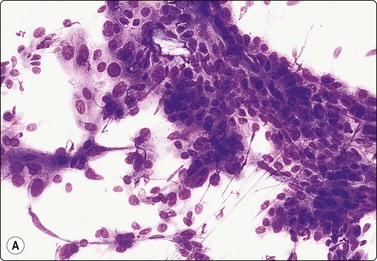

A 60-year-old woman with a history of right mastectomy for cancer 4 years previously presented with a lump in the right axilla. It was described as subcutaneous by the surgeon who performed the FNB and the clinical diagnosis was metastasis of breast cancer. Smears were highly cellular, of epithelial cells both forming cohesive aggregates and dispersed as single cells. True papillary fragments were not seen. The cells had a moderate amount of dense cytoplasm and there was relatively mild nuclear atypia (Fig. 14.10). The pattern was considered to be in keeping with metastasis of a low-grade breast carcinoma. However, the nodule was, in fact, intracutaneous and the histology was reported as syringocystadenoma papilliferum (Fig. 14.10).36

image image image

Fig. 14.10 Syringocystadenoma papilliferum

Clustered and dispersed epithelial cells; moderate amount of cytoplasm; mildly atypical nuclei; no true papillary fragments (A, MGG, HP; B, H&E, IP); (C) Corresponding tissue section (H&E, LP).